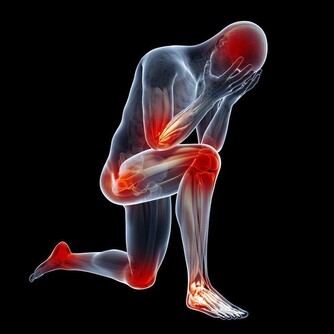

生活中的行為、活動,既需要靠體內陽氣提供能量和動力,也需要體內的陰精提供物質給養。

如果長期“過勞”,且得不到及時的修復和養護,會導致動力系統的效能降低,腎陽耗損,腎自然就傷了。